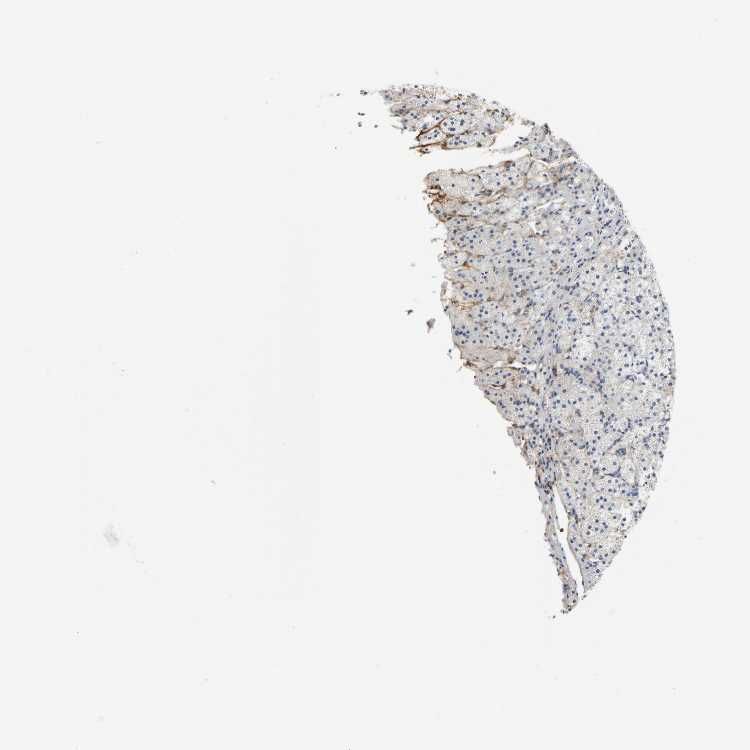

ADRENAL GLAND - Antibody stainingi

Antibody staining in the annotated cell types in the current human tissue is reported as not detected, low, medium, or high, based on conventional immunohistochemistry profiling in selected tissues. This score is based on the combination of the staining intensity and fraction of stained cells.

Each image is clickable and will lead to virtual microscopy that enables deeper exploration of all samples and also displays staining intensity scores, fraction scores and subcellular localization as well as patient and tissue information for each sample.

Antibody HPA004625Antibody CAB002417

Glandular cells Not detectedNot detected